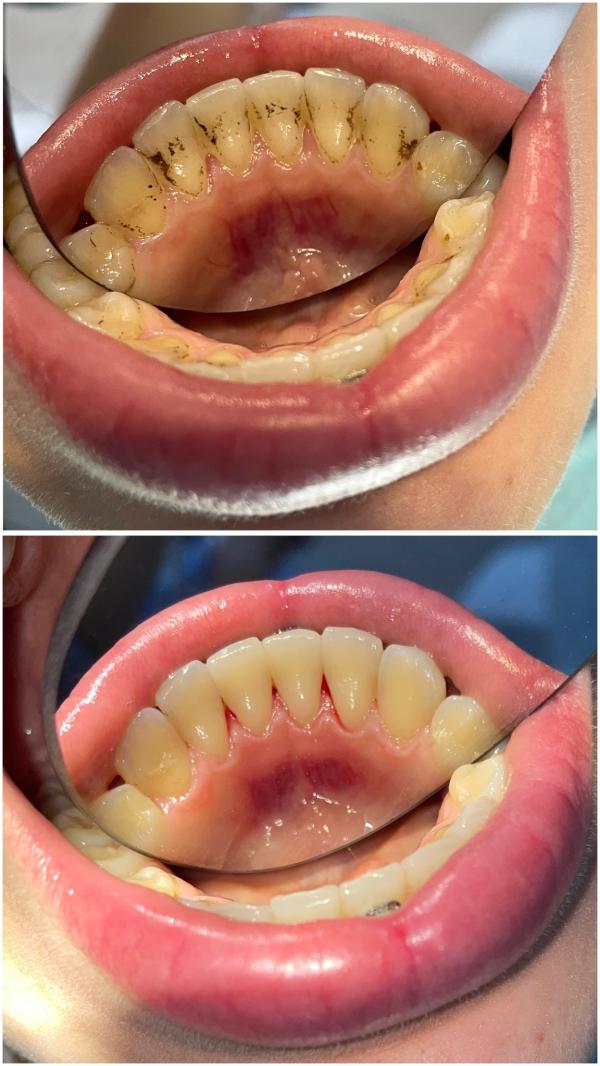

Профгигиена полости рта в Дербенте: цены для взрослых и детей

post image 2

Завтра есть окошки на профгигиену полости рта🌷🦷

Цена 2500₽

Детям 1500-2000₽